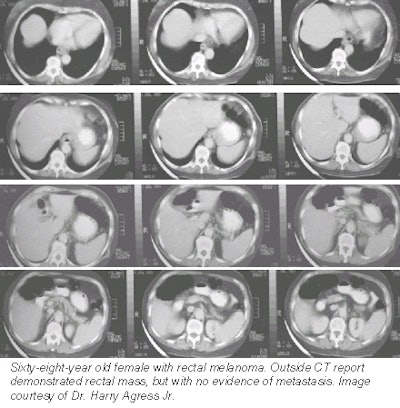

An extensive case experience at HUMC has proven PET's ability to detect cancers missed on CT scans. In one case, an outside CT study of a 68-year-old woman with rectal melanoma (see below) showed a rectal mass, but with no evidence of metastases. A PET study performed two weeks later at HUMC, however, revealed hepatic and pulmonary metastases.

![]() |